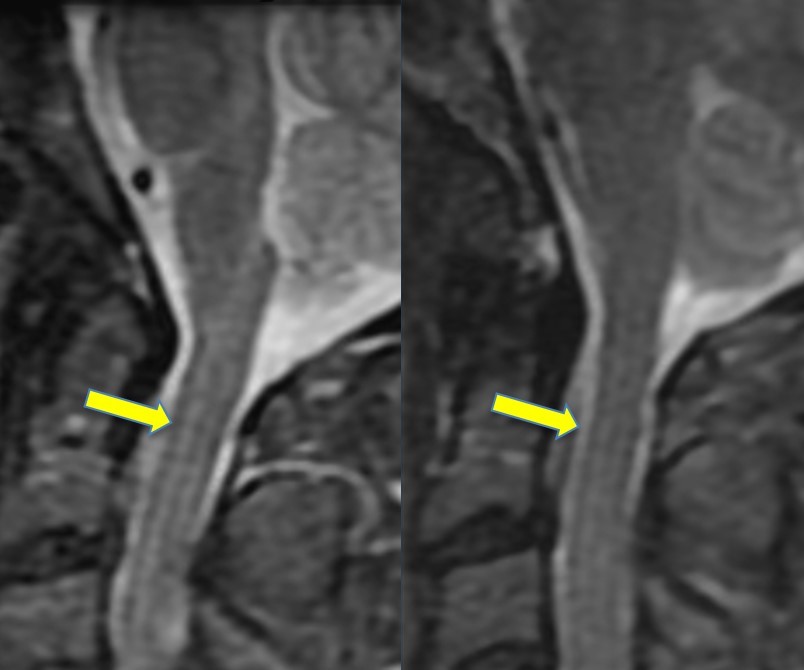

How can Gibbs artifact be minimized

Truncation errors (Gibbs artifact) can be minimized by increasing the number of phase-encode steps or by reducing the field of view.

What was the most likely step taken to eliminate the artifact seen in the first image?

Increasing the matrix size decreased truncation artifact (aka Gibbs, or ringing).

choosing a smaller FOV can also help eliminate this artifact